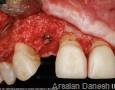

Surgery